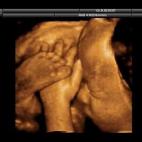

En esta galería puedes ver en fotos como es el desarrollo de un feto de semana en semana:

Desarrollo del feto, en fotos

Ver la galería